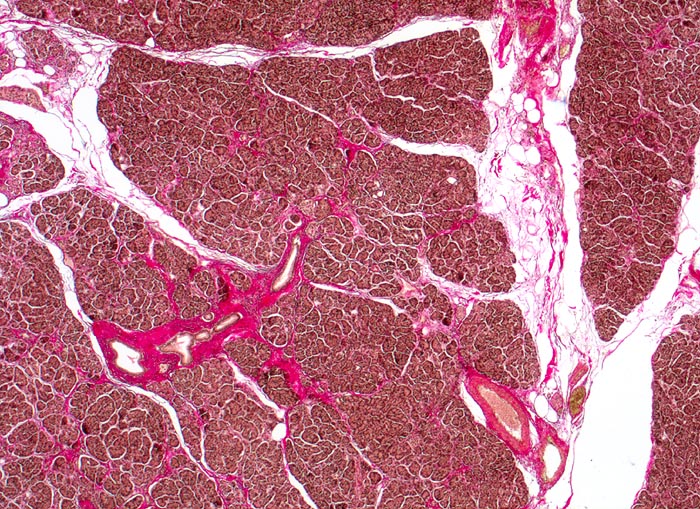

• Rechts oben Reste von nicht neoplastischem Pankreasparenchym mit fokaler chronisch obstruktiver Pankreatitis als Folge von tumorbedingten Gangobstruktionen: Vollständige Atrophie des exokrinen Pankreas bei erhaltenen Inseln. Ersatz des atrophen Parenchyms durch Fibrose. Chronisches Entzündungsinfiltrat.